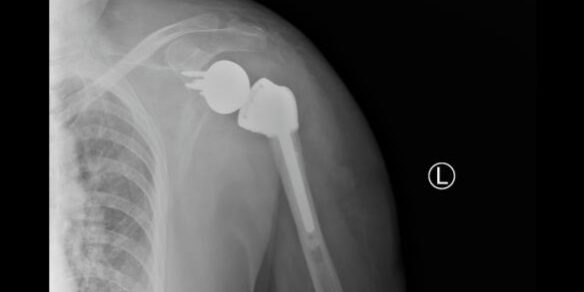

X光片显示肩关节假体在位良好

术后患者状况良好,第二天即可开始下地活动,肩关节也可以做一些简单的前后运动,X光片显示肩关节假体在位良好,目前患者已康复出院。